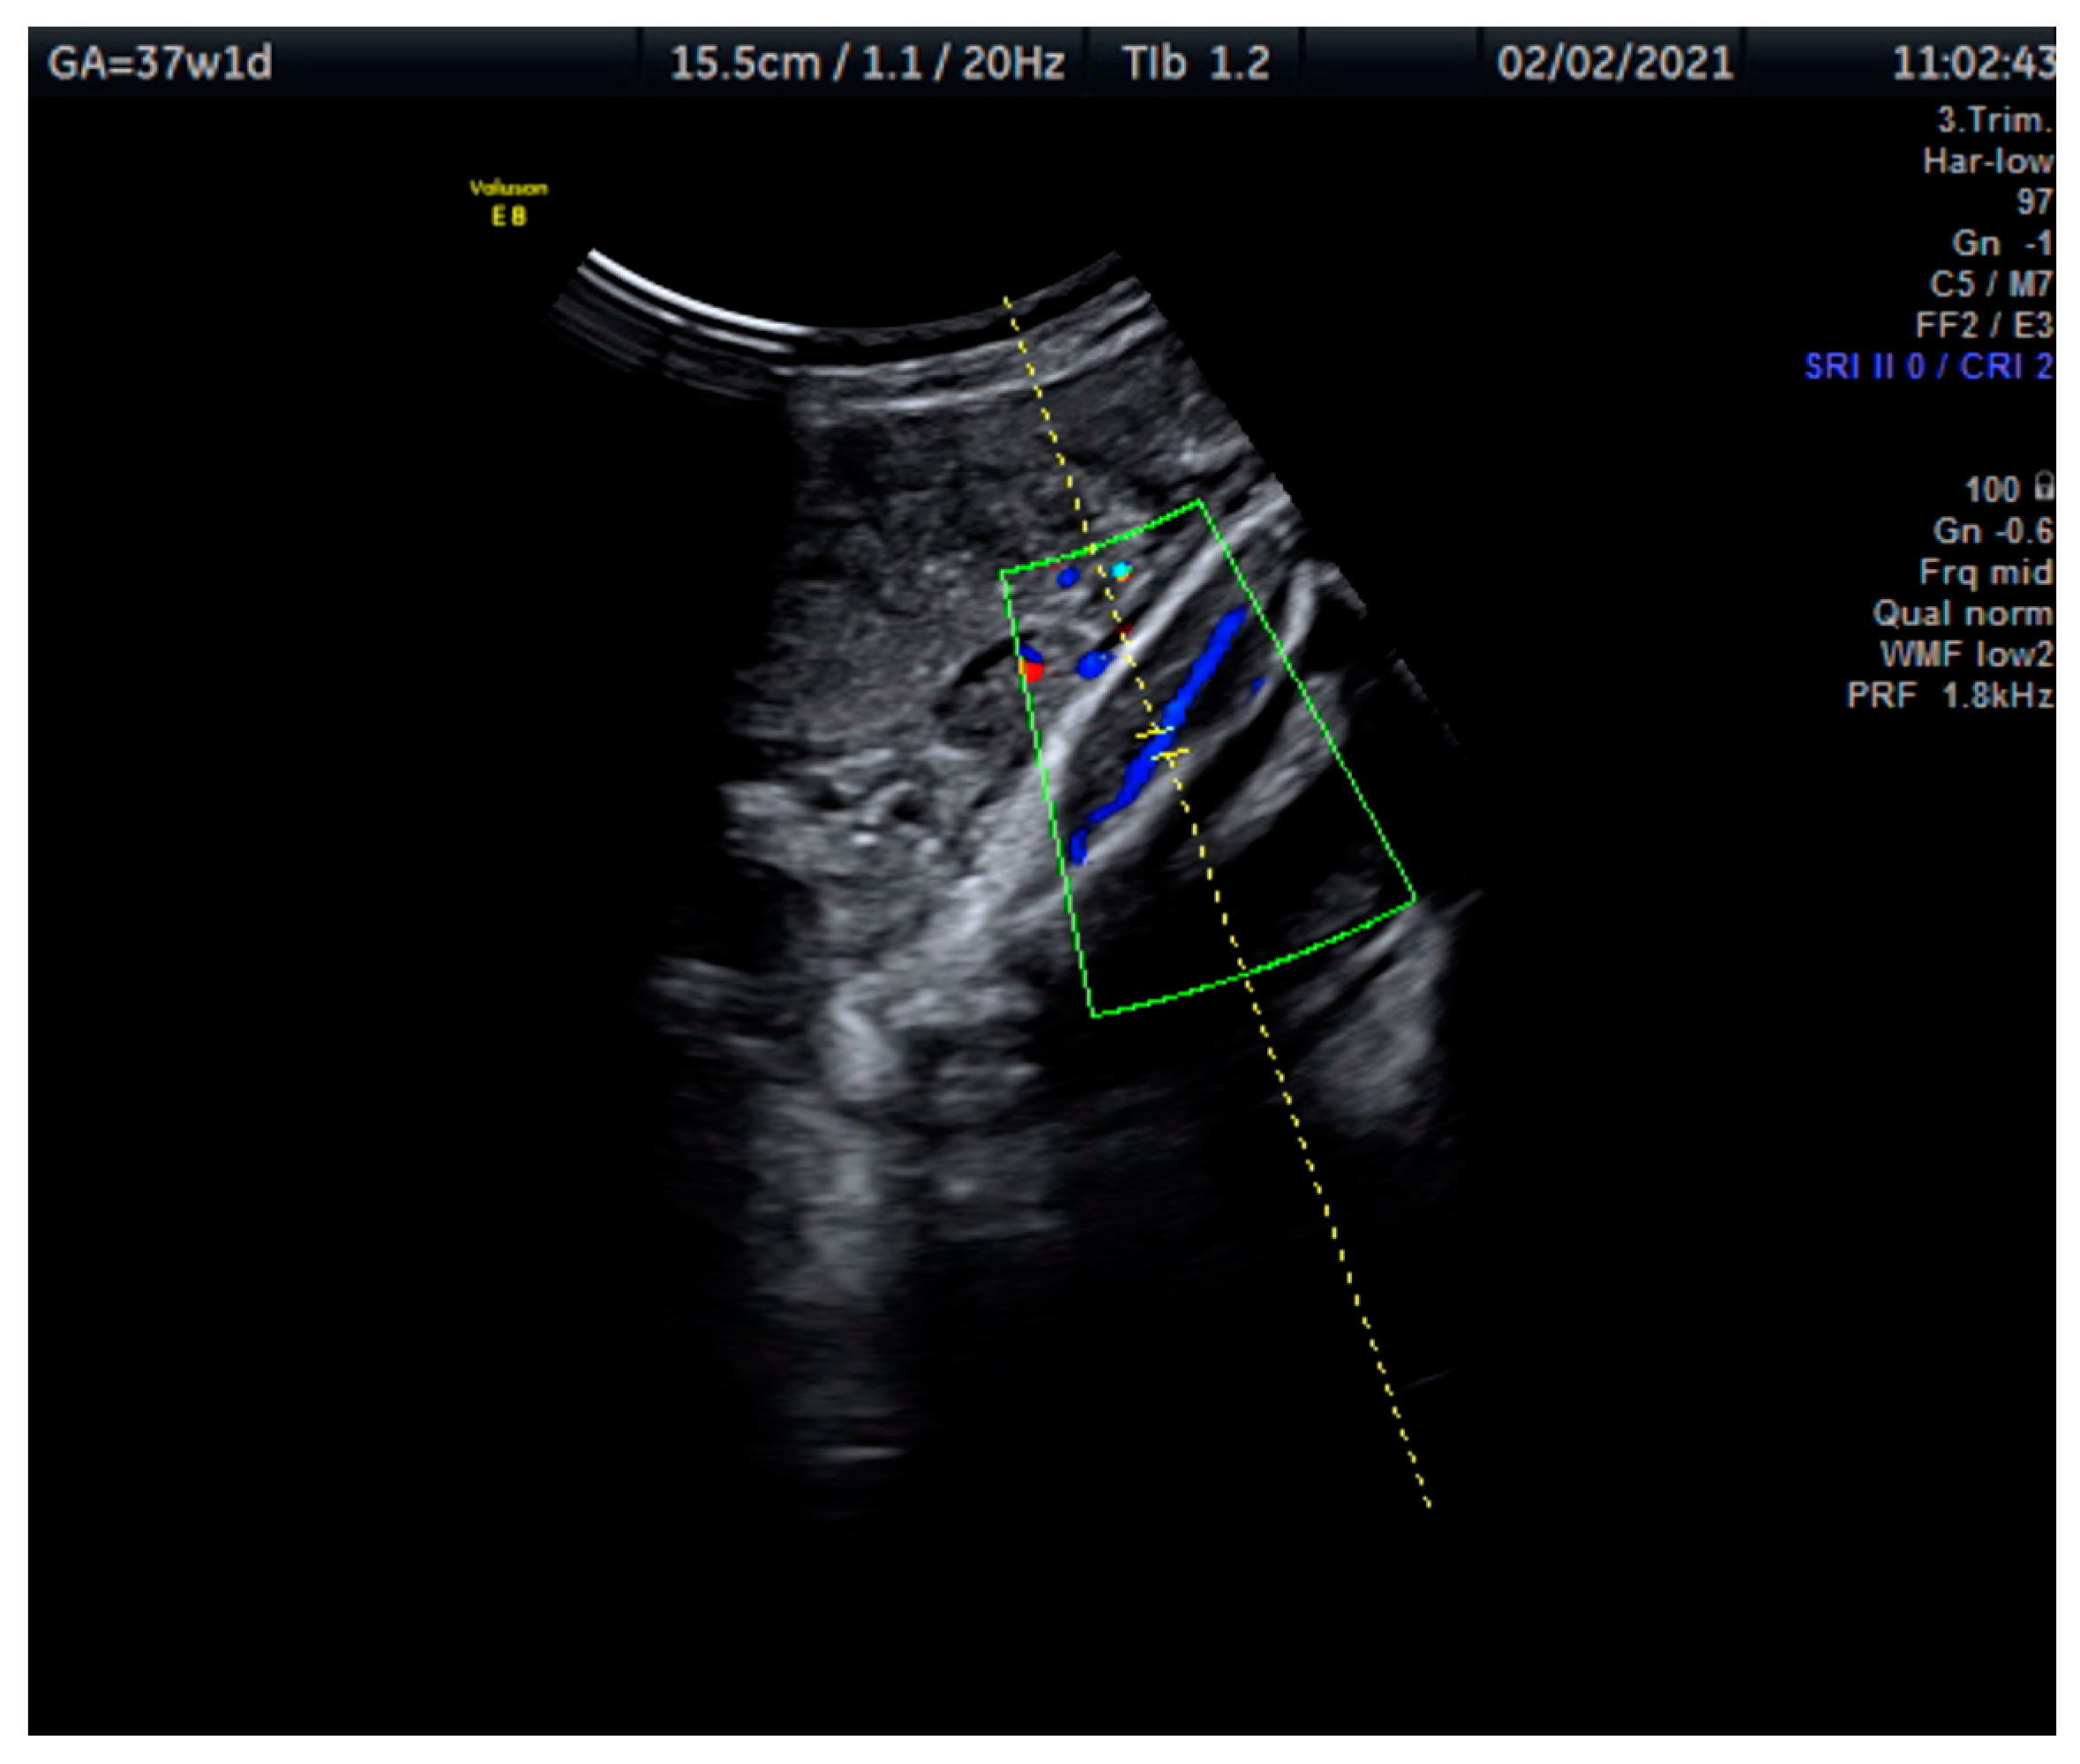

Measurements of the TA-PI were taken using Doppler on the lower extremity where the tibial and fibular bones were clearly visible. The angle between the transducer and the bones was adjusted to 45° or less. The color Doppler gate was placed over the vessel in the leg between the two bones to locate the anterior TA (Figure 1). We were able to measure the velocity of the TA in all fetuses, signals were recorded over at least 5–6 cycles with an equal shape and amplitude of the blood flow waveforms (Figure 2 and Figure 3).

Figure 1.

This Doppler image shows the technique of the measurement of the blood flow of the tibial artery of the fetal lower extremity with the tibial and fibular bones clearly visible. The measurement was taken at 37 + 1 weeks.